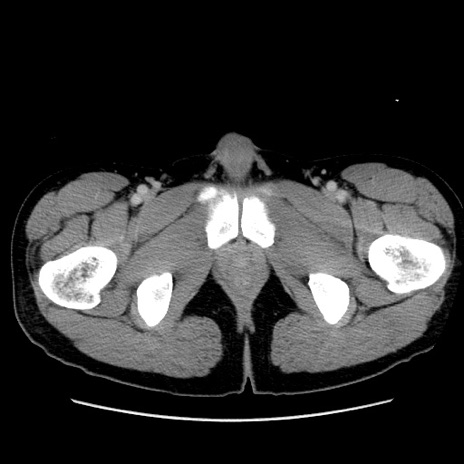

冠状断像

【症例】20歳代 男性

【主訴】心窩部痛

【現病歴】今朝より上腹部痛あり。一旦軽快していたが再度出現したため救急要請。昨日夕に白身の魚を含む刺身を食べた。

【身体所見】BP 136/89mmHg、HR 74/min、BT 37.0℃、腹部:膨満、軟、心窩部に圧痛あり。反跳痛なし、筋性防御なし、腸雑音やや亢進あり。

【データ】WBC 17700、CRP 0.48